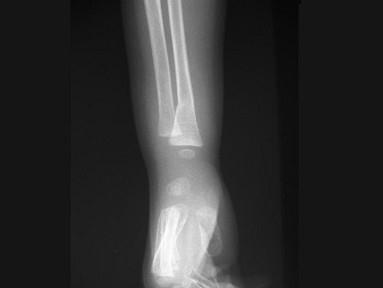

出生6个月的男婴,摔地后右手红肿,请结合CR片,选出骨折类型 ( )A、粉碎性骨折B、压缩骨折C、横行骨折D、斜行骨折E、青枝骨折

问题 出生6个月的男婴,摔地后右手红肿,请结合CR片,选出骨折类型 ( )

选项 A、粉碎性骨折 B、压缩骨折 C、横行骨折 D、斜行骨折 E、青枝骨折

答案 E